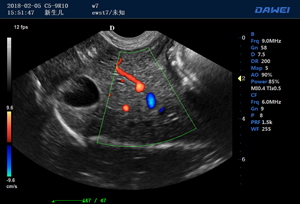

S80高端便攜獸用彩超-彩色多普勒多普勒超聲診斷儀掃描圖 S80高端便攜獸用彩超-彩色多普勒多普勒超聲診斷儀 S80高端便攜獸用彩超-彩色多普勒多普勒超聲診斷儀